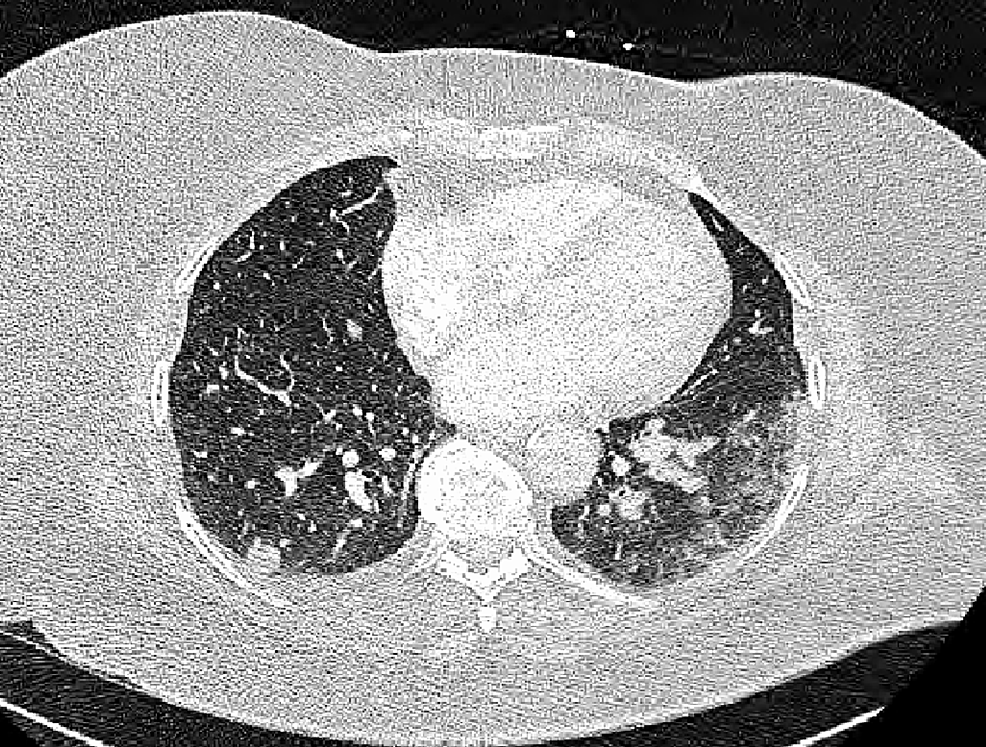

multiple nodules lung ct Consolidation lung ct bilateral pleural Breast Cancer And Multiple Lung Nodules Metastatic cancer is the main cause of multiple lung nodules, especially in people with a family history of cancer. This study sought to investigate the incidence, clinical characteristics and outcomes of patients with indeterminate. When cancer that started in the breast spreads to 1 or both lungs, it’s called secondary or metastatic breast cancer in the lung. It is most. Breast Cancer And Multiple Lung Nodules.